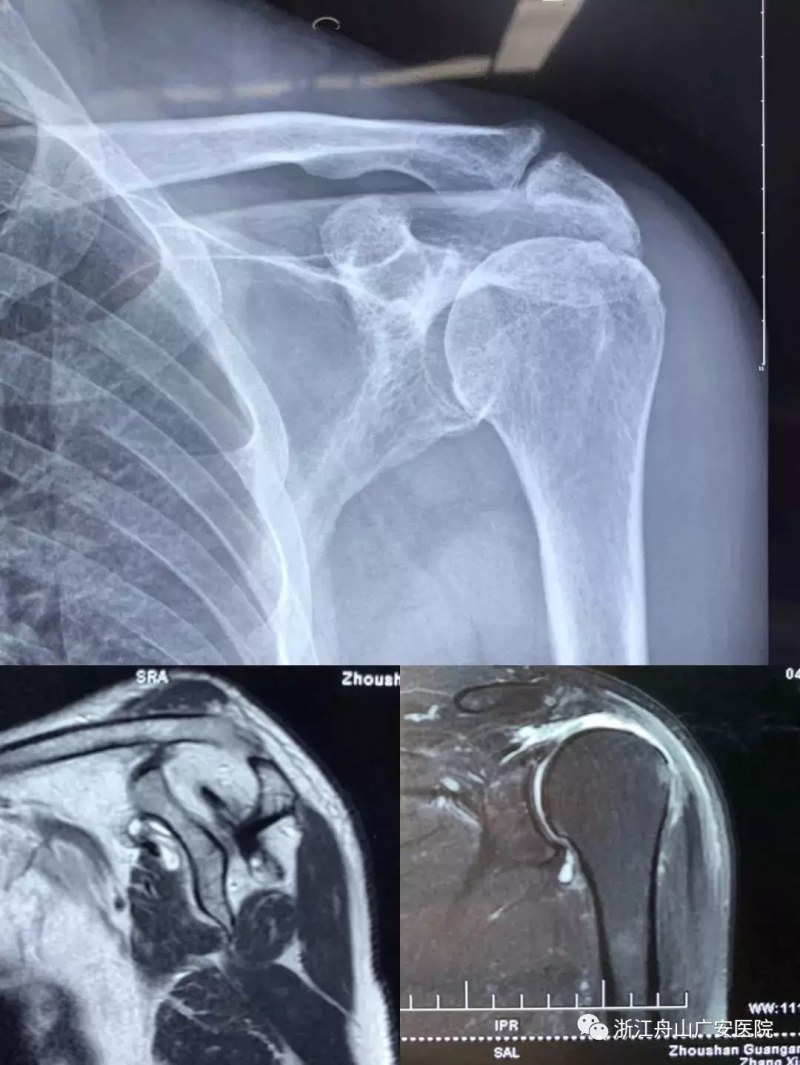

张大伯一年前因右肩巨大肩袖断裂,曾在我院行关节镜微创手术,术后恢复非常满意。现患者要求进一步行左肩关节手术治疗入院,经过广安医院常务副院长危立军、关节科及运动医学科罗军主任的详细检查,患者为左肩巨大不可修复肩袖撕裂关节病,肩袖的脂肪浸润达到四级,常规的微创手术治疗不能恢复患者的肩膀功能,只能通过特殊类型的人工肩关节——反式全肩人工关节来重建关节功能。

反式肩关节置换术后照片